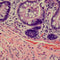

Pathologist: “Can you see that this slide from yesterday is exceptionally good? The nuclei are stained dark blue, and you can see nuclear detail. The eosin is staining in three distinct shades of pink. This is a really excellent slide.”

Pathologist: “Now, can you see that this slide from today is very pale? The nuclei are stained a faint blue and you can’t see nuclear detail. The eosin appears washed out. This is an awfully bad slide, and I cannot make a diagnosis from it.”